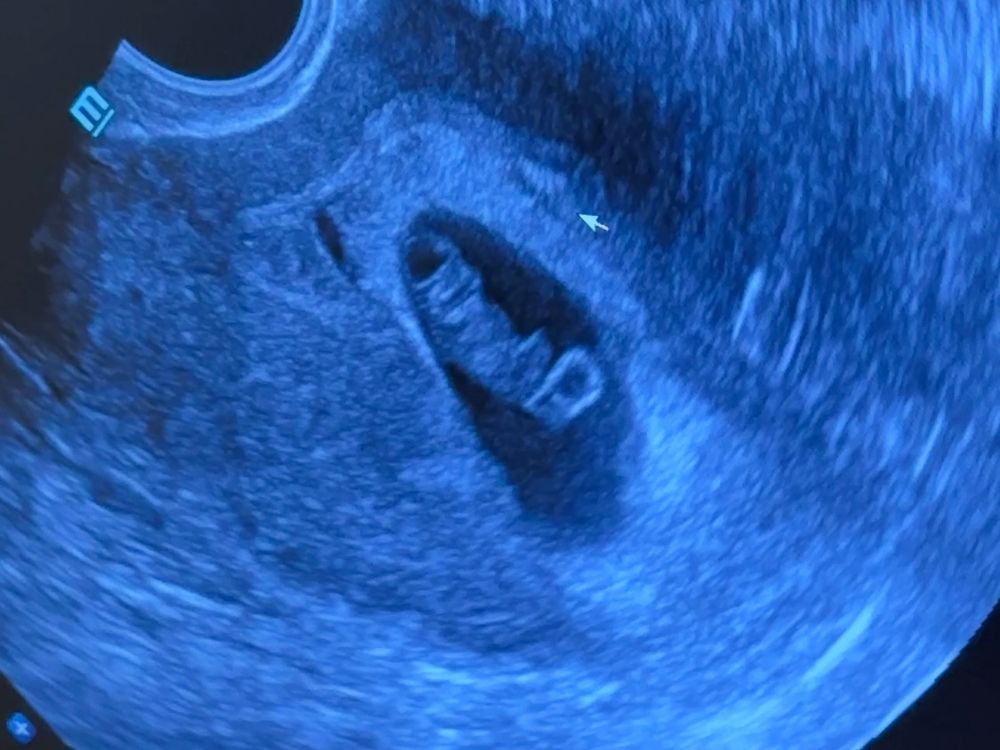

У меня такой же ктр,но по фото кабачок😂 у вас прям человечек Изображение

25.06.2024

ИзображениеВот наша самая свежая фотка 10+4, странная конечно фотка ну да ладно, скоро на 1 скрининг будет точно что-то удачнее.